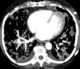

Pulmonary artery angiosarcoma